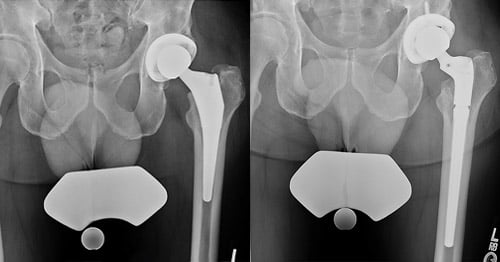

X-ray images of hip revision before and after.